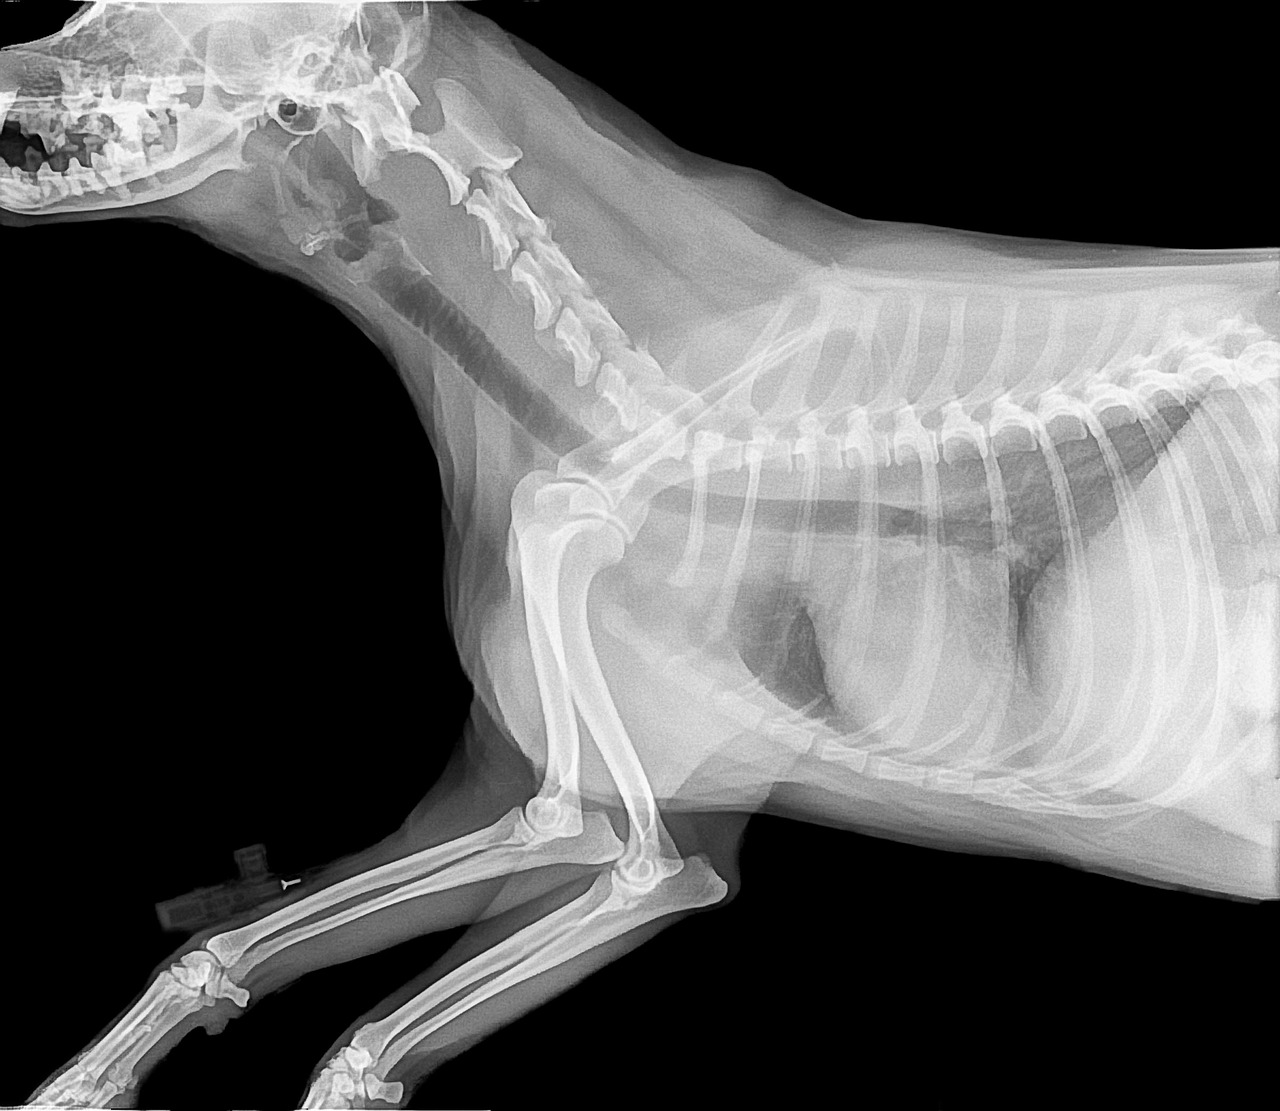

Before splinting a broken bone in your pet, having the right materials is essential. Using items in your home can make a significant difference in the splinting process. Some common materials include cardboard, wooden sticks, or commercially available splints designed for pets. Make sure that any material you choose is rigid enough to provide support yet flexible enough not to cause injury. The padding is equally important; this can be achieved with soft towels or cloth to prevent your pet’s skin from being irritated by the splint. A good combination of materials will help create a well-supported splint that minimizes discomfort. Additionally, keep a roll of cohesive bandage or soft tape handy for securing the splint in position. Avoid using adhesive tape that could damage the pet’s fur or skin. When preparing your supplies, clean them with appropriate disinfectants to reduce the risk of infection. Have sterile wipes or antiseptic available to treat any open wounds. Finally, familiarize yourself with the anatomical structure of your pet’s limb to enhance your effectiveness and confidence during the procedure.

Fitting the splint requires attention to detail and technique. Placing the splint incorrectly can lead to improper healing or further injury. Start by ensuring that the splint covers the joint above and below the fracture; this helps immobilize the area effectively. Do not rush this crucial step, and take your time to ensure proper alignment. The next step is to wrap the padding around the bones and joints before applying the splint. Always check for signs of swelling or restricted blood flow after placing the splint. Loose splints may shift or fall off altogether, while tight splints can cause serious harm. Adjusting your technique according to the size and breed of your pet is essential. Always maintain a calm atmosphere to avoid startling them, which may lead to sudden movements causing further injury. It may be helpful to have a friend assist you. Following these guidelines can make a vital difference for your pet’s recovery while strengthening their trust in you as a caregiver.